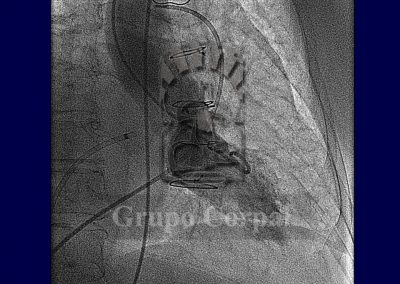

This circuit is not always necessary in the case of aortic paravalvular leaks. It is sufficient to cross the leak backwards from the aorta, leave the guide lodged in the left ventricle and take the cannula there to insert the Amplatz device in the distal portion, then releasing the middle and the aortic portion. When the correct position is ensured by angiography and ultrasound, the device is released and occludes the leak.

From a technical perspective, this is a complex procedure, and only experienced teams can perform it. Under general anaesthesia, with haemodynamic and transoesophageal ultrasound monitoring, the objective is to cross the regurgitation site with a hydrophilic guide, and use it to establish a venous-arterial circuit with the two ends. We thus take a cannula to the leakage point with an Amplatz device (Nitinol). Once the distal part is in the exterior, the cannula and device are pulled with ultrasound and scopy control. When the distal part has been put correctly with gentle pull, the waist and proximal part are then extracted. Once we are sure that the position is correct, the device is released from the carrier wire.